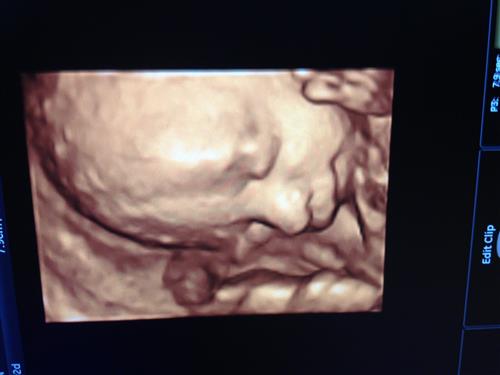

Team green

jaclyn78

3/19/13

1